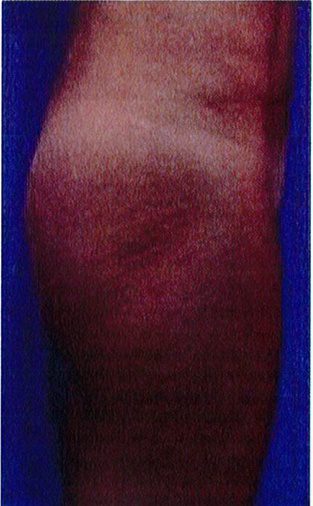

Hình. 18.. (A) Hình anh trước và (B) và sau phẫu thuật làm đầy mông của bệnh nhân được đặt khối implant dưới cân thể tích 225 mL, hai bên.

Bệnh nhân 31 tuổi tiền sử khỏe mạnh, có chỉ định nâng mông bằng implant do thiếu hụt thể tích. Hai khối anatomic implant 225 mL polyurethane dạng gel được đặt ở vị trí dưới cân. Sau phẫu thuật không ghi nhận biến chứng trong suốt quá trình hồi phục, vết mổ liền tốt (Hình 18).

Bệnh nhân 52 tuổi xuất hiện chùng da vùng mông (mức độ nặng), mong muốn giải quyết vấn đề này đồng thời tăng kích thước vòng ba. Hai khối anatomic implant

Hình. 19. . (A) Hình anh trước và (B) và sau phẫu thuật làm đầy mông của bệnh nhân chùng da vùng mông tương đối nhiều. Bệnh nhân được đặt khối implant dưới cân thể tích 330 mL ở hai bên.